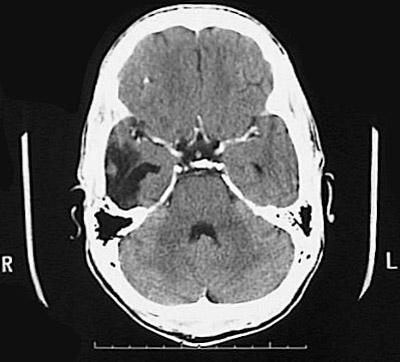

Click on the area of hemorrhage in the CT scan below:

This CT scan demonstrates a large area of hemorrhage in the right temporal lobe as a consequence of a ruptured vascular malformation.